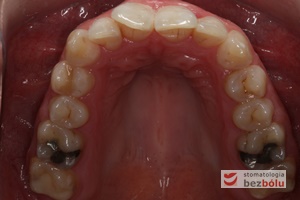

Leczenie bezekstrakcyjne z wykorzystaniem strippingu

Pacjentka lat 22 zgłosiła się do naszej placówki celem podjęcia leczenia ortodontycznego. Głównym oczekiwaniem pacjentki była poprawa estetyki uśmiechu oraz brak ekstrakcji zębów na drodze do jej uzyskania. Ze względu na liczne stłoczenia zębów w górnym i dolnym łuku, dość duży materiał zębowy w porównaniu z bazą kostną, a także zgryz przewieszony boczny prawostronny po dokładnej analizie cefalometrycznej oraz analizie modeli diagnostycznych zastosowano leczenie bezekstrakcyjne z wykorzystaniem strippingu jako alternatywy dla usuwania zębów, mającego na celu uzyskanie miejsca w łuku na uszeregowanie zębów. Po fazie aktywnego leczenia trwającego 18 miesięcy zastosowano leczenie retencyjne w postaci szyny retencyjnej w łuku górnym oraz retainera stałego w łuku zębowym dolnym klejonego od kła do kła.